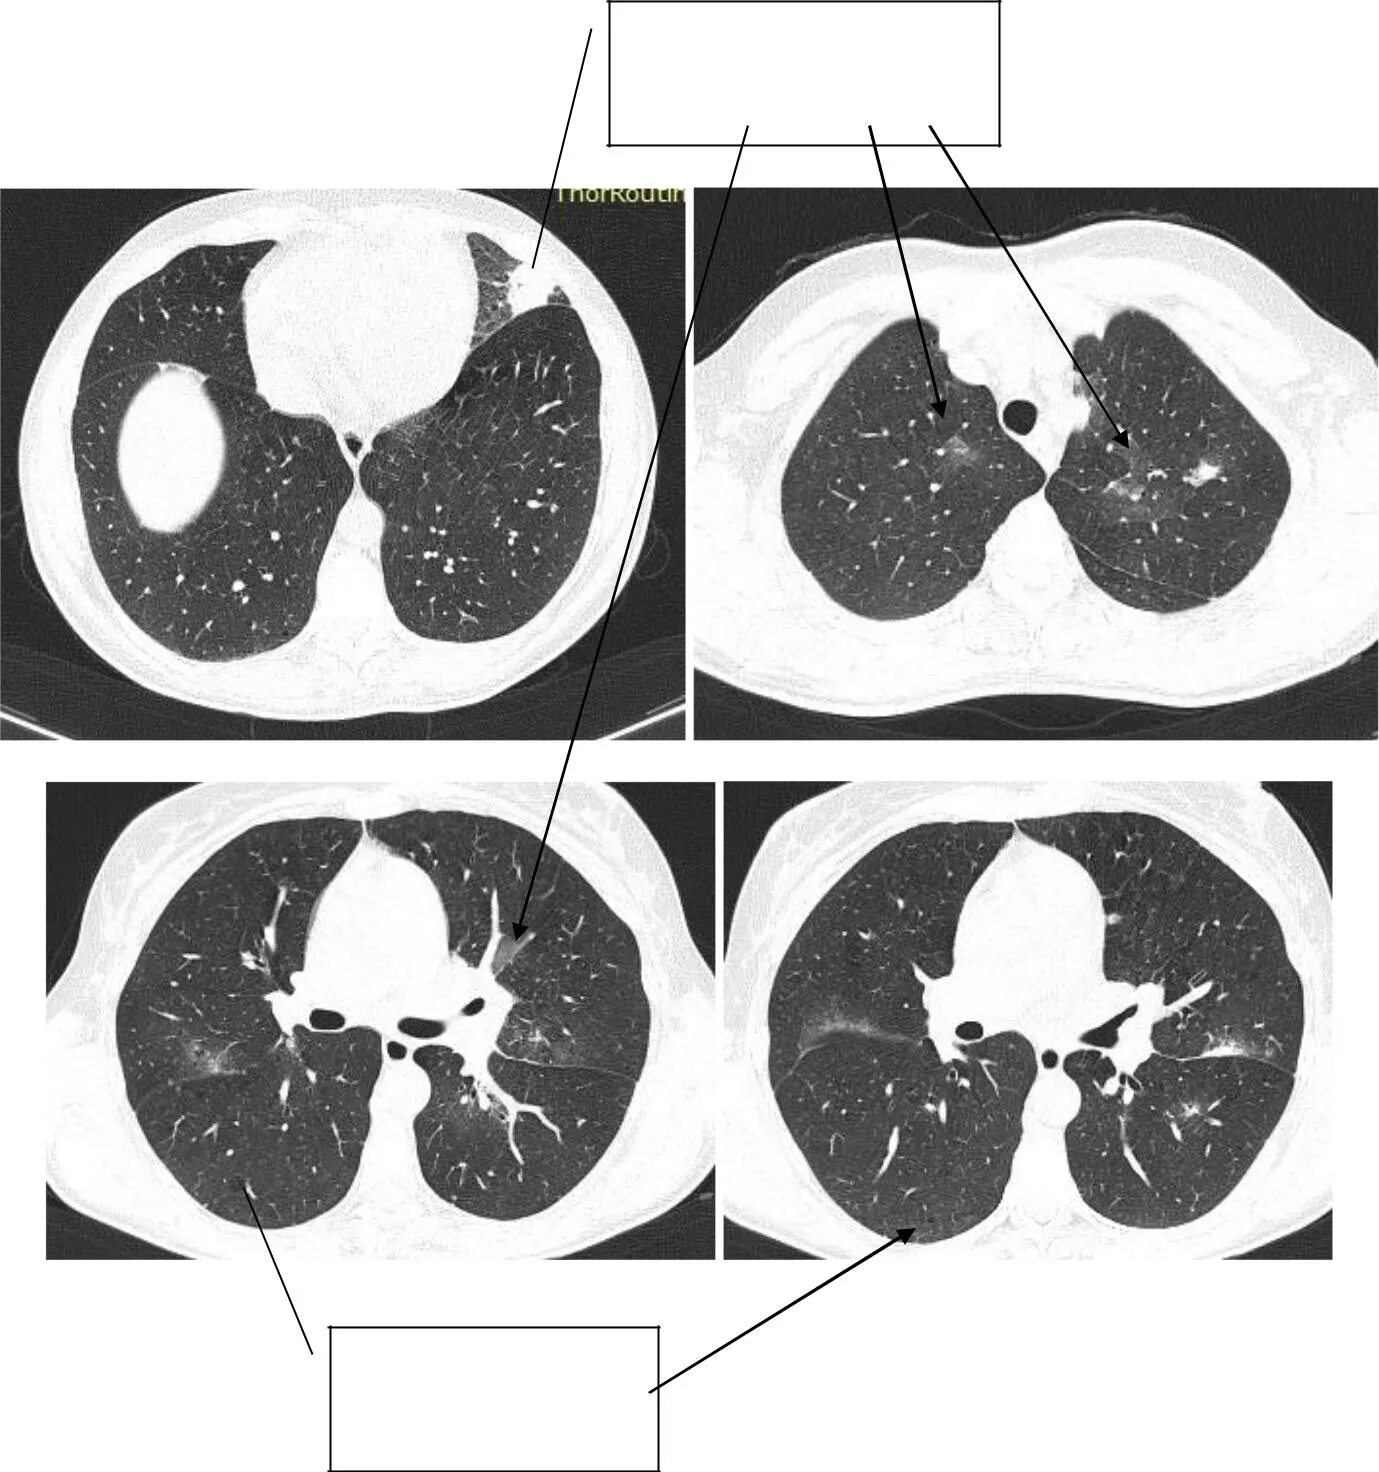

Как выглядит пневмония на кт